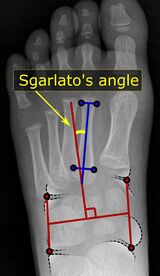

A Sgarlato's angle of more than 15° indicates pigeon toe.[9]

Pigeon toe can be diagnosed by physical examination alone.[10] This can classify the deformity into "flexible", when the foot can be straightened by hand, or otherwise "nonflexible".[10] Still, X-rays are often done in the case of nonflexible pigeon toe.[10] On X-ray, the severity of the condition can be measured with a "metatarsus adductus angle", which is the angle between the directions of the metatarsal bones, as compared to the lesser tarsus (the cuneiforms, the cuboid and the navicular bone).[11] Many variants of this measurement exist, but Sgarlato's angle has been found to at least have favorable correlation with other measurements.[12] Sgarlato's angle is defined as the angle between:[9][13]

• A line through the longitudinal axis of the second metatarsal bone.

• The longitudinal axis of the lesser tarsal bones. For this purpose, one line is drawn between the lateral limits of the fourth tarsometatarsal joint and the calcaneocuboid joint, and another line is drawn between the medial limits of the talonavicular joint and the 1st tarsometatarsal joint. The transverse axis is defined as going through the middle of those lines, and hence the longitudinal axis is perpendicular to this axis.

This angle is normally up to 15°, and an increased angle indicates pigeon toe.[9] Yet, it becomes more difficult to infer the locations of the joints in younger children due to incomplete ossification of the bones, especially when younger than 3–4 years.[citation needed]